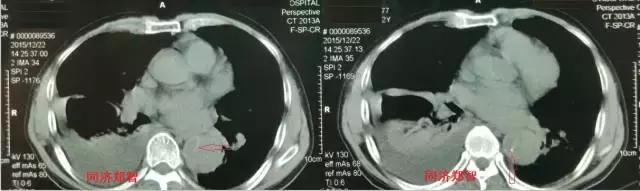

病例四

腹部平扫CT提示腹主动脉增宽,CTA证实为腹主动脉局限性夹层(红箭头所示)。